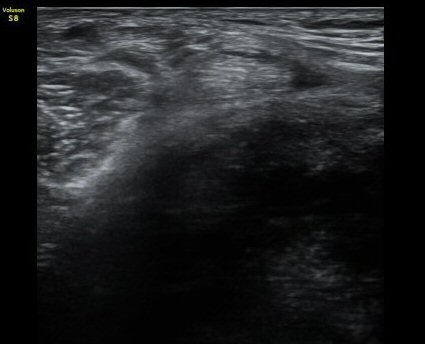

¹«¸­ µÚ ³»Ãø ¹Ý¸·¾çÈûÁÙ(semimembranosusu) Á¾´Ü¸é°Ë»ç¿¡¼­  ÈûÁÙÀÇ ºñÈÄ, ÈûÁ٠ǥÃþÀÇ ¼ö¾×

Àú·ù¿Í ÈûÁÙ ºÎÂøºÎ °æ°ñÀÇ ºÒ±ÔÄ¢ º¯È­°¡ °üÂûµÊ(±×¸² 3).

¹«¸­ µÚ ¹Ý¸·¾çÈûÁ٠Ⱦ´Ü¸é °Ë»ç¿¡¼­ ÈûÁÙÀÇ ºñÈÄ¿Í ÈûÁ٠ǥÃþ¿¡ ¼ö¾× Àú·ù°¡ °üÂûµÊ(±×¸² 4).